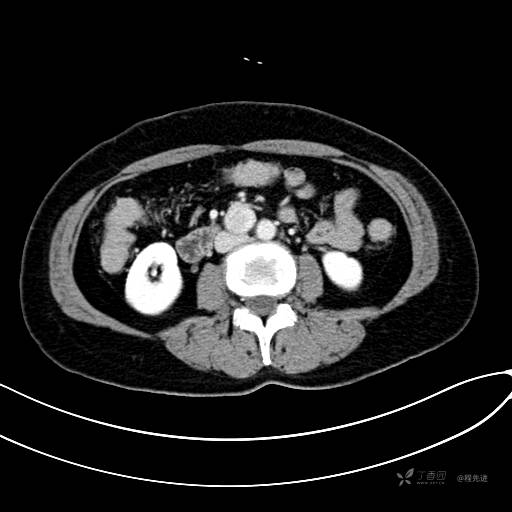

CT增强动脉期